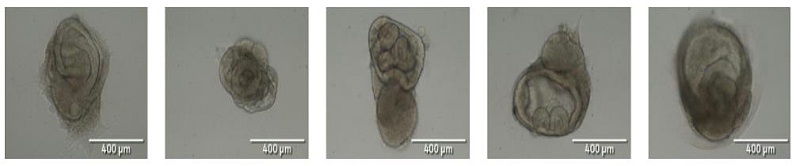

在球體嵌入 ATCC 細(xì)胞基底膜并保存在類器官生成培養(yǎng)基中后的 7 天內(nèi),大的簡單圓形類器官變得可見,直徑約為 100-200 μm。到第 30 天時,類器官的大小和復(fù)雜性大大增加,直徑為 1500-2000 μm,并且有許多可見的管狀和隱窩/芽狀結(jié)構(gòu)。